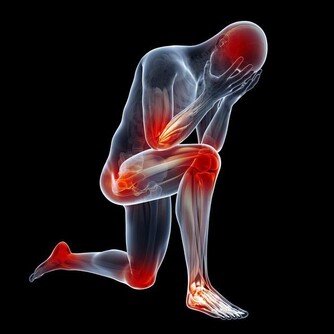

5. 多運動

說起來容易做起來難,但運動確實有助於降低血糖。此外,運動可以幫助增強肌肉,增加能量,改善睡眠和情緒。你的目標是每週約150分鐘的中度運動,而且要分三天以上完成。如果可能,還應該每週兩天進行抗阻訓練。